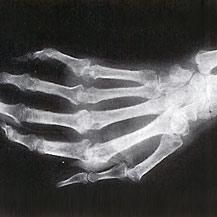

- Si suele amanecer con las manos rígidas e inflamadas, intente dormir con un par de guantes ajustados. Así puede ayudar a mantener la inflamación bajo control. Pero deje de hacerlo si al dormir con guantes empeora la inflamación matutina.